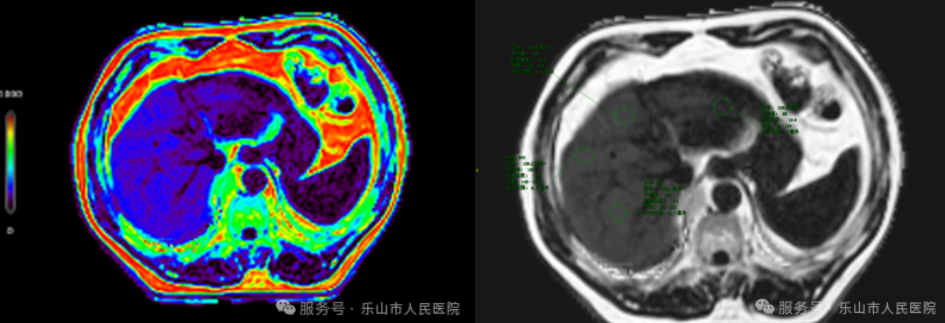

那么,有没有精准度高又不那么痛苦的方法呢?(鱼和熊掌我都要)!还真有!现在就有一种叫磁共振质子密度脂肪分数(MRI-PDFF),可以直接测量肝脏脂肪含量的百分比,诊断的精准性跟“居”一针的结果差不多。另外,穿刺采集仅限于局部肝脏,而MRI-PDFF能够还可以精准地对比复查动态监测。值得一提的是MRI-PDFF检查无辐射,只要没有MRI禁忌症(这个医生会协助您确认),所以你看肝脏“胖不胖”这事真不是小事!它正悄无声息地影响着越来越多的人,连瘦子也不能掉以轻心!